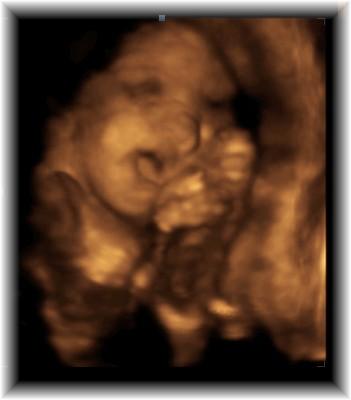

hey mädels mal wieder eine meldung von mir sorry das ich mich jetzt erst melde hab aber wieder viel mit übelkeit zu kämpfen und müdigkeit könnte nur schlafen war heute mal beim 3 d und siehe da wir haben das gesicht und die hände sehen dürfen mein fa meinte auch neulich er wäre sich sicher das es ein junge wird wobei die ärtzin meint ein mädchen mal sehen müssen am montag wieder zum fa ultraschall machen und schauen ob es immer noch ein kleiner prinz ist... und dann noch das erste mal ctg bei der hebamme die auch in der praxis ist, ist die frau von unserem doc..,

Bild zu mein kleiner sonnenschein - Forum für September - Mamis

nochmal eins

Ach goooooott - ist das niedlich :) Gähnt es da grade? Hihi, ich freu' mich, dass Du jetzt eine so schöne Erinnerung an dieses Stadium der SS hast! LG, Tiffy

Oh mein Gott!!! Ist das niedlich!!! Das sind wirklich schöne Bilder? In welcher Woche bist du denn jetzt? Lg Karina

25 ssw haben es dreimal versucht und heute ging es endlich und dankeschön für die lieben komplimente